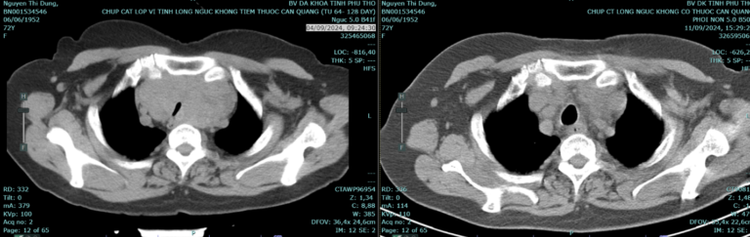

Rất may mắn là khi tiến hành phẫu thuật cho người bệnh, kíp mổ đã không phải thiết lập hệ thống tuần hoàn ngoài cơ thể và cưa xương ức. Ê kíp bác sĩ phẫu thuật đã cắt được toàn bộ u qua đường mổ nếp lằn cổ.

| Hình ảnh khối u bướu tuyến giáp thòng trung thất và khí quản bị ép xẹp do khối u Sau mổ khối u đã được lấy hết và khí quản đã bình thường - Ảnh BVCC |

Sau phẫu thuật, người bệnh tỉnh, nói tròn tiếng, kích thước vùng cổ về bình thường. 9 ngày sau người bệnh đã ổn định, ăn uống, đi lại bình thường, nói rõ ràng và được ra viện.